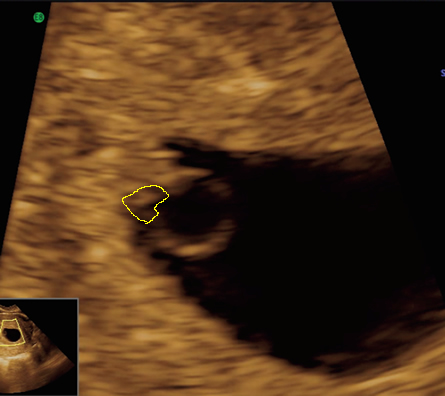

At 6 weeks

Anatomy on transabdominal ultrasound at 6 weeks

Although the detail of the embryo is not as clear if we scan through the abdomen, we can still make out quite a lot of the important features. Click on the thumbnails to see what features of the embryo are visible.

| Fig 1 This is a magnified view of a transabdominal ultrasound image |